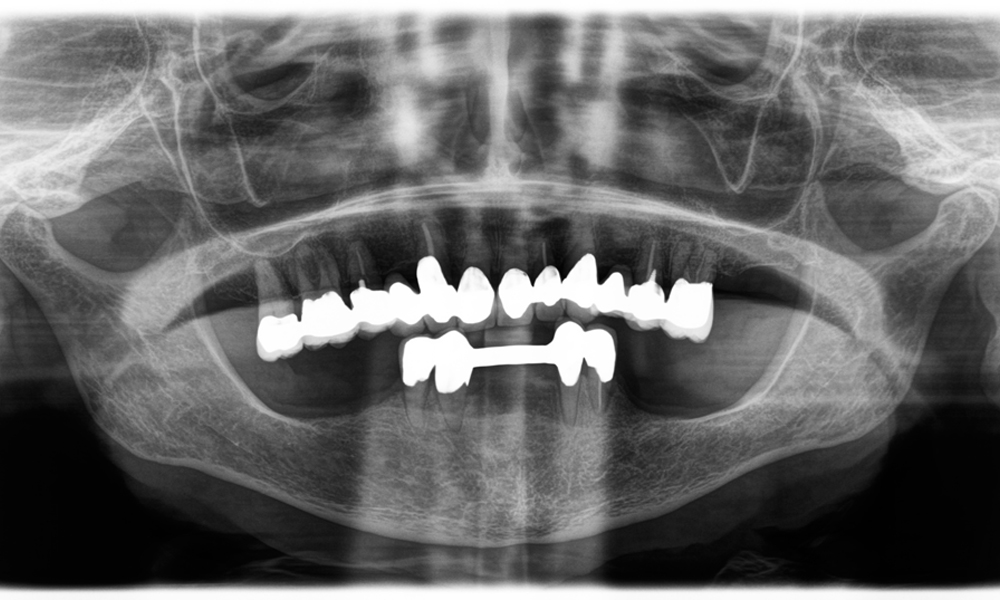

A jaw x-ray from an 81-year-old patient, in front of a black background.

Figure 1: Aesthetic rehabilitation of PFM crowns: Complete removal and replacement of 40-year-old PFM crowns to improve aesthetics in an 81-year-old patient.